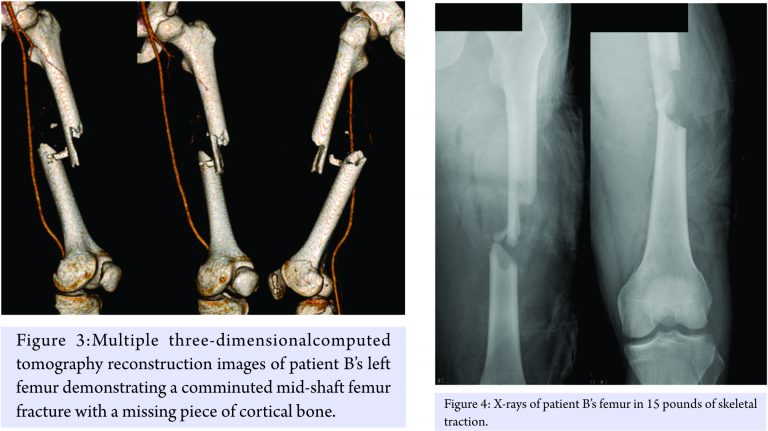

Attention was then turned to patient B. He was also awake and neurovascularlyintact. He was found to have a 6 cm wound to his left thigh. Radiographs and CT angiogram were performed, and the patient was found to have an open, comminuted, mid-shaft femur fracture with a missing piece of cortical bone and no vascular injury(Fig. 3). He was also found to have a fracture of the lateral pole of the patella as well as a coronal split of the lateral femoral condyleon the ipsilateral extremity. His wound was irrigated in the trauma bay, and he was placed in 20 pounds of proximal tibial skeletal traction. Post-traction radiographs further revealed cortical bone loss of the femoral shaft(Fig. 4).On further evaluation of both patients’ imaging studies, the missing cortical fragment from patient B’s femur was ejected and impaled patient A’s proximal tibia.

The decision was made to treat both patients operatively. First, patient A was taken to the operating room for an exploration and debridement of the left knee with there moval of the cortical piece of bone, followed by a retrograde intramedullary femoral nail. A spanning knee external fixator was placed to stabilize his tibial plateau fracture. The removed cortical fragment was identified as the missing piece of bone from the other patient’s femur (Fig. 5 and 6).